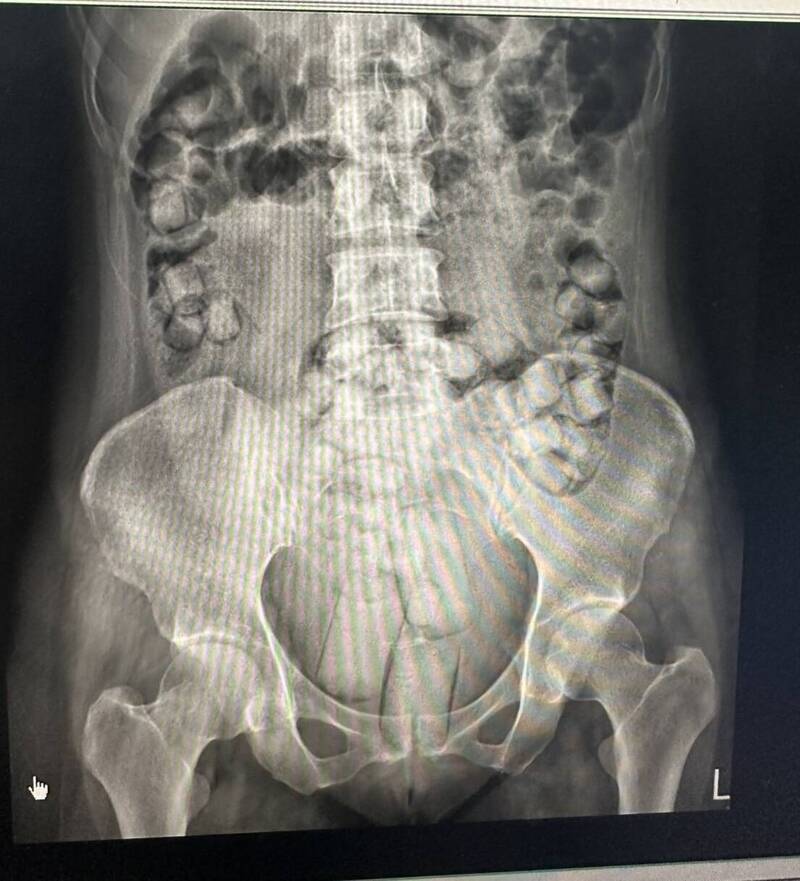

Shockingly, the drugs were found to have been packed into pieces of plastic shaped into balls and strips before being swallowed or inserted into their anus.

To smuggle the drugs, the syndicate packed small amounts of heroin into waterproof, transparent films before covering each with a condom to prevent it from being corroded by stomach acid.

They then packed these into oval-shaped balls and long strips so they could be easily swallowed and inserted into the anus.

The women were found with over 50 packs of pure drugs inside each of their bodies and were subsequently sent to Kaohsiung Hospital to remove the drugs by undergoing enemas.

Coast Guard personnel said the smaller balls of drugs were swallowed with olive oil, while the larger ones were inserted into the anus with lubricant.

Woman A was found with 54 balls of heroin, weighing 390.93 grams, while woman R had 61, which weighed 273.07 grams.

According to TVBS, the drugs that the women had smuggled into the country are enough to supply about 25,000 people and cost approximately NT$8.3 million (S$342,000).